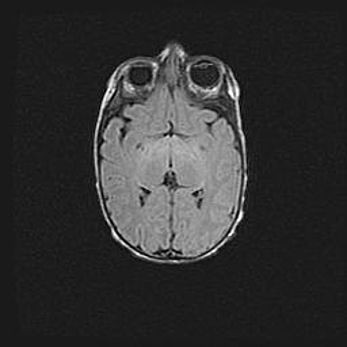

Ниже представлена  галерея МРТ снимков, полученных с применением LMT неонатальных матричных РЧ катушек. Также каждая группа МРТ снимков сопровождается информацией о пациенте (диагноз, возраст, вес, пол, срок гестации) и краткой сопроводительной расшифровкой диагноза.

Церебральная ишемия II.

Возраст: 5 дней

Вес: 3400 г

Пол: женский

Окружность головы: 35 см

Срок гестации: 39 недель

Церебральная ишемия – это заболевание, характеризующееся недостаточностью (гипоксией) либо полным прекращением (аноксией) снабжения мозга кислородом по причине закупорки одного или нескольких сосудов. Это приводит к  что метаболическим расстройствам различной степени тяжести в тканях головного мозга, развитию коагуляционных некрозов и гибели нейронов.